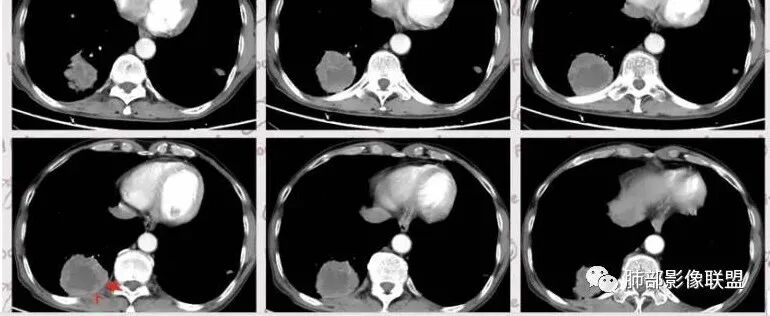

老年男性,肺气肿背景,结核病史。右肺下叶病灶,分叶不明显,局部可疑栽赃,毛刺略呈毛刷感,远端阻塞性肺炎改变,轻微强化,走行血管僵硬,湖泊样坏死,考虑鳞癌。左肺病灶边缘有分叶、毛刺及胸膜牵拉的恶性征象,也有平直收缩的良性征象,可疑卫星灶,这类良恶征象都有判断比较纠结,常规思路:炎性放前边,腺癌待排。

临床病史很长,背痛9年可能与左侧胸膜炎有关。两上肺陈旧性结核伴肺气肿没有问题。左下肺病灶,分叶毛刺、胸膜凹陷、指状凸起,增强轻度强化,腺癌问题不大。右侧附加题有些困难,病灶内血管显影,不像结核的表现,先把结核否掉?鳞癌和慢性脓肿的鉴别:支持良性的征像,低密度区内也有细小血管影,不像鳞癌坏死?与胸膜关系整体还是比较和谐,边缘还算光整,毛刺都在远端,不支持慢性脓肿的的地方,周围支气管管壁都很干净。恶性征像,与支气管的关系图片给的不够。坏死边缘不光整,有些浅分叶。总体,我觉得坏死区血管的存在更有价值,验证一下,右侧首先考虑慢性脓肿。

右下肺实性病灶,进入病灶支气管阻塞,支气管壁增厚,病灶内可见坏死,内壁凸凹不平,增强可见病灶强化,考虑恶性病变,鳞癌?

老年男性,结核、慢性病史,肺气肿背景,右肺胸膜下肿块影,边界清晰,边缘膨隆,中度环形强化,内见边界清晰坏死区,并见部分强化小血管,鳞癌破坏力强,而且病灶一侧支气管受推移,首先考虑右肺结核,鉴别鳞癌,左肺考虑腺癌,胸膜牵拉,膨隆生长,边缘毛刺样,潜在分叶。

老年男性,既往肺结核病史。肺气肿背景,可见钙化灶及条索影。右肺下叶胸膜类圆形占位,边界清晰,内部可见边界清晰的坏死区,轻度强化,考虑为结核可能;左肺下叶结节,可见分叶,毛刺,胸膜牵拉,增强可见强化,考虑为恶性,腺癌可能。

左肺肺气肿,双肺多发结节,上肺多发纤维索条影及钙化,符合陈旧性结核病变。右肺下叶结块,边缘毛糙,内部可见低密度坏死,环形强化,坏死边界清楚,考虑脓肿,OP。左肺下叶结节,边缘可见毛刺,深分叶,边缘收缩,远端牵拉胸膜,考虑肺癌,腺癌。

老年男性,肺气肿背景,左肺下叶结节,深分叶,毛刺,胸膜牵拉,内部可见坏死,坏死边界不清,不均匀强化。右肺下叶大肿块,边缘有毛刺,多发小灶性坏死,胸膜下有侵犯,考虑恶性,左肺下叶腺癌,右肺下叶低分化鳞癌。

男,64岁,咳嗽咳痰,气喘10余年,右肺下叶软组织密度肿块影,边界清晰,边缘见细短毛刺及分叶,轻度胸膜粘连,病灶内密度不均,增强扫描看见坏死区,病灶边缘明显强化,考虑鳞癌可能。左肺下叶病灶深分叶、毛刺、胸膜牵拉,考虑腺癌可能,除外转移性病变。

双肺陈旧性肺结核,肺气肿背景。右肺下叶肿块,边缘毛糙,内部可见大片低密度坏死,环形强化,坏死边界清楚,考虑鳞癌。左肺下叶结节,边缘可见毛刺,深分叶,有收缩,有膨隆,胸膜牵拉,考虑腺癌。

1.左侧分叶深一些

2.右侧糊墙

左侧胸膜凹陷

3.左侧支气管显示欠佳,似乎在门口堵塞

右侧支气管门口堵塞,有推移迹象

4.右侧坏死明显,内部囊变坏死边缘部分清楚、部分不清

左侧坏死不明显

主要征象:病灶分叶不明显、较光整,局部胸膜栽赃,支气管门口堵塞,有推移迹象;增强后坏死明显,内部囊变坏死边缘部分清楚、部分不清楚,病灶内可见血管,局部稍毛糙,实性部分强化较明显,总体考虑恶性病变。一部分征象指向鳞癌(支气管截断、坏死较多,病灶内血管破坏),但又有肉瘤的一些特点(病灶较大,缺乏分叶,坏死边界清晰),要考虑到肉瘤样癌。

3、本病好发于60岁以上的老年男性,多数有吸烟史。周围型多于中央型,病灶边缘较清楚,多数光整圆钝,部分可见浅分叶,少数有毛刺,无胸膜凹陷征出现。CT平扫时呈软组织密度,较小的肿块密度较均匀,肿块较大时中央常出现坏死。增强扫描肿块多呈斑片状不均匀强化,而肿瘤周边厚薄不均的囊壁样强化较具特征性。周围型多数位于胸膜下,常常侵犯胸膜或胸壁。